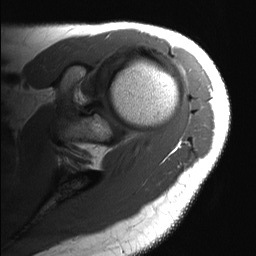

deltoid muscle glenoid labrum

glenoid

glenoid labrum

long head of biceps brachii muscle

middle glenohumeral ligament

buford variant

anterior labrum

posterior labrum